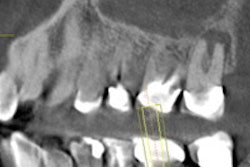

Recommendation: A panoramic radiograph with bitewings is appropriate. Both can be used as a guide for any further imaging such as a periapical radiograph of a tooth with a deep restoration. For the average new dental patient, a panoramic radiograph with bitewings is advisable.

In the situation in which the dentist doesn't have access to a panoramic system, then selected periapicals plus bitewings are advised. However, if the patient has clinical evidence of generalized dental disease or a history of extensive dental treatment, then a full-mouth series is most appropriate.

The third case is the patient with generalized disease and extensive dental treatment in the past. In this scenario, a full-mouth series is in order. The same would also be true for a patient with active periodontal disease.

In these cases, while a panoramic radiograph with bitewings might result in a lower radiation dose, it would not provide enough information to manage the patient properly. Here, the proper use of selection criteria would result in an increase in radiation dose, but the additional information would justify that increase.